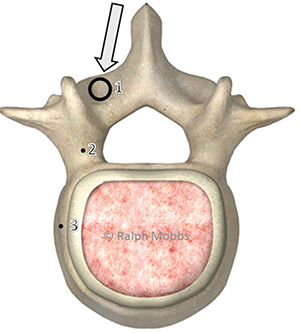

Fig. 2 Model showing the starting point for the MLST technique

(point 1). Points 2 and 3 demonstrate the trajectories that the

surgeon can use during lateral or AP radiography.

Fig. 3 Model showing the axial trajectory for the MLST screw (arrow).

The screw follows a medial to lateral path, thus avoiding lateral

dissection of the paraspinal musculature.